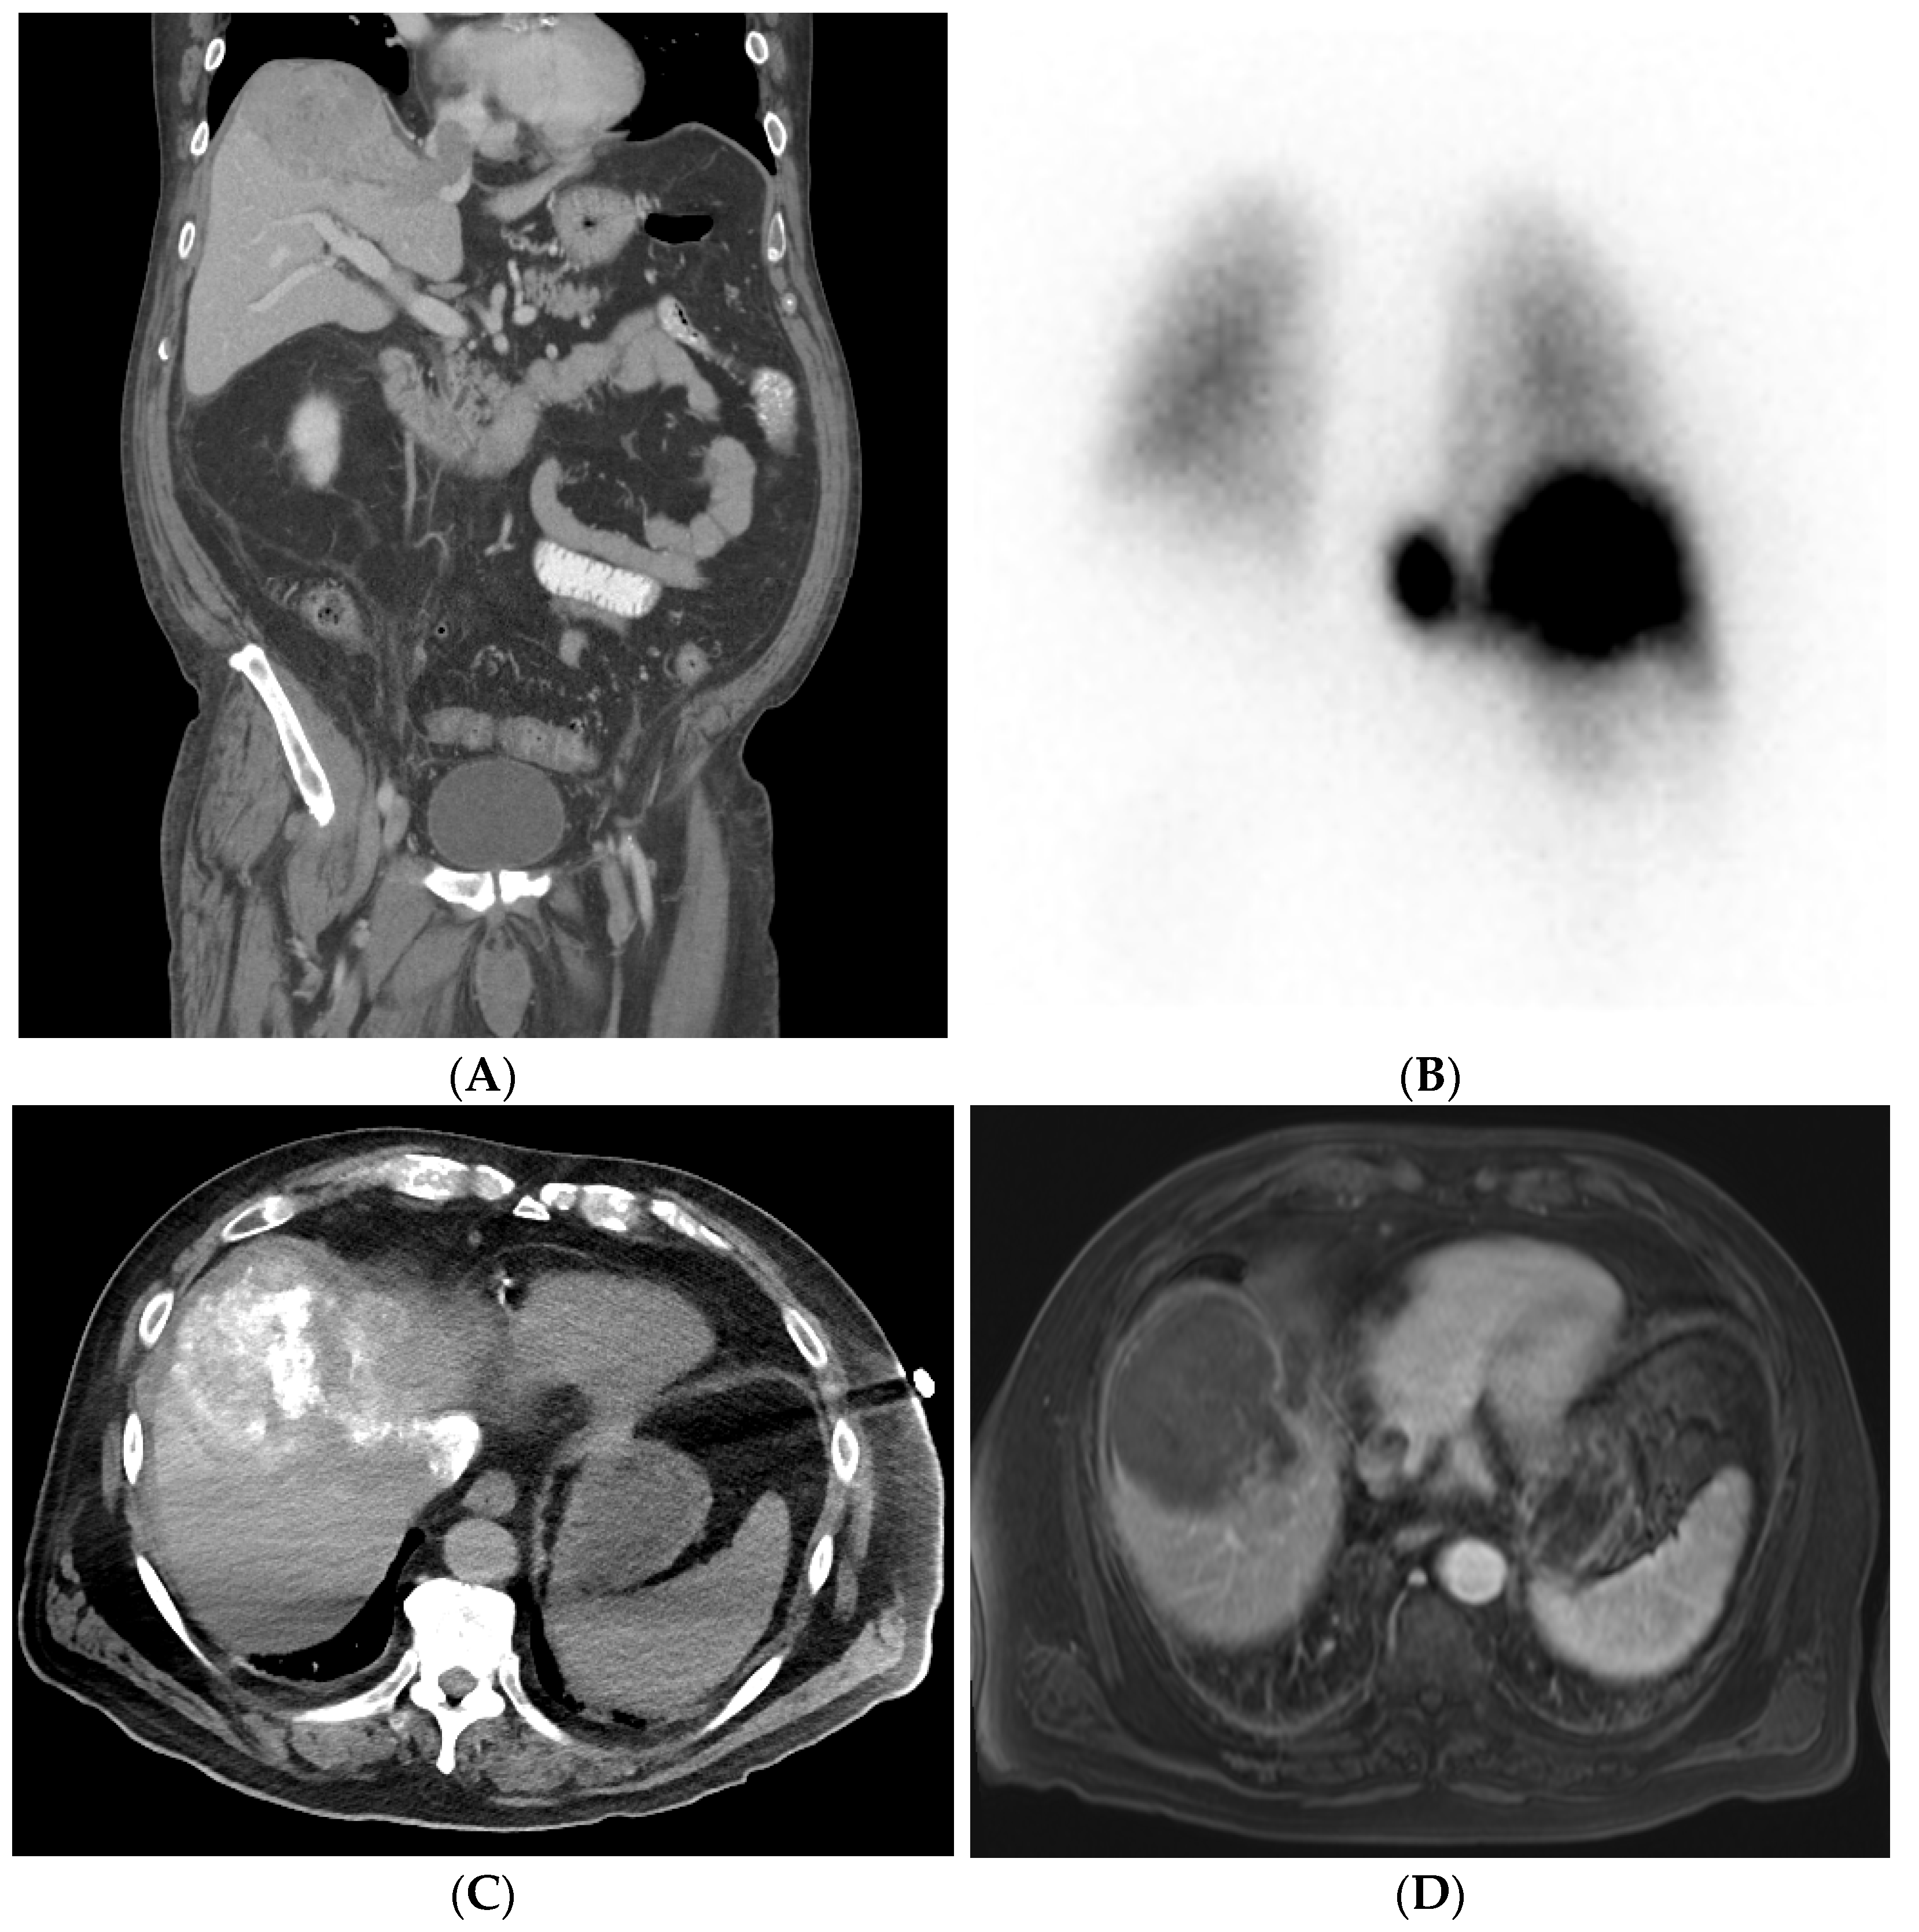

6.1. Pretreatment Imaging

- Schraml, C.; Kaufmann, S.; Rempp, H.; Syha, R.; Ketelsen, D.; Notohamiprodjo, M.; Nikolaou, K. Imaging of HCC-Current State of the Art. Diagnostics 2015, 5, 513–545. [Google Scholar] [CrossRef] [PubMed]